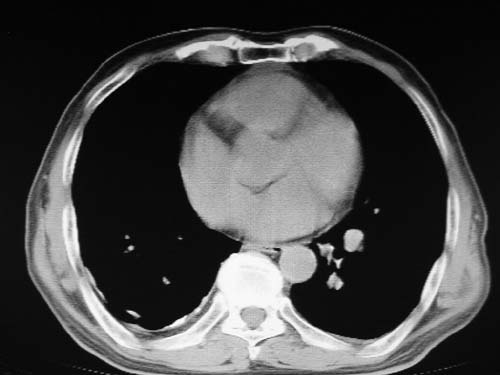

男,80岁

左肺动脉异常增粗,考虑肺动脉狭窄可能。

右肺上叶继发性肺结核。

右侧胸膜增厚、钙化,左侧胸膜反应。

肺动脉高压,左肺动脉瘤样扩张。